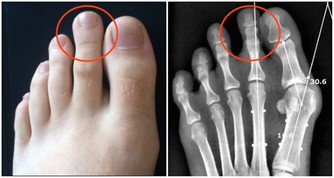

他迅速撥打120, 將蘇煜拉到了當地一家醫院,經檢查醫生拿著拍的片子說,「這治不了,肺都爛了。」蘇先生便帶著兒子趕到了省胸科醫院。 網咖人員聚集、空間密閉,易感染結核病菌 在省胸科醫院內,醫生通過檢查確診,蘇煜患的是嚴重肺結核,大部分肺已經被結核菌侵蝕掉。同時,他還伴有胸腔積水、上消化道出血。 經過一系列治療後,蘇煜逐漸甦醒過來。面對父母,他說得最多是「後悔」。 「前一段時間,剛接診過一個病人,也是20歲左右的小夥子,因為長期泡網吧,結果感染上了結核性腦膜炎,到醫院不到兩天就死了。」省胸科醫院一位醫生說。 「集聚的人群,密閉的空間,很容易感染結核病菌。」這位醫生說,上網容易導致疲勞、自身免疫系統功能下降,再加上網咖的人員流動性大,空氣環境不好,一旦有一個傳染源,網吧裡的其他人很容易感染上。 網吧的空氣質量到底有多差?河南電視台《民生大參考》通過專用的雷射粉塵儀,實地檢測了一下當地市區部分網咖的空氣品質,結果讓人震驚!有網吧的pm2.5濃度最高的達到了2.1毫克每立方米,也就是2100微克每立方米!!